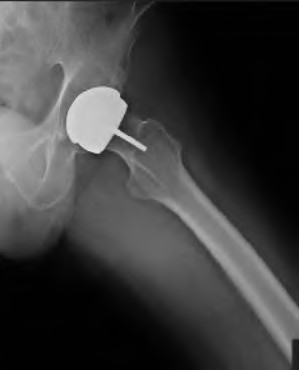

A 72-year-old male presents 2 years status post fixation of an impending pathologic right femur fracture due to metastatic renal cell carcinoma. He is minimally ambulatory due to pain. Despite radiation therapy, there has been progression of the lesion with extensive cortical bone loss, which is shown in Figure A. A proximal femoral replacement arthroplasty is performed without complications, and is demonstrated in Figure B. Which of the following is true regarding this patients post-operative course?

Deep prosthetic infection is the most common complication after hip arthroplasty performed for salvage of failed internal fixation after pathologic proximal femoral fracture secondary to malignancy.

Jacofsky et al reviewed the complications in 42 patients with a mean age of 63 who were treated with hip arthroplasty for salvage of failed treatment of a pathologic proximal femoral fracture. Multiple different constructs were used.

The most common complication was deep prosthetic infection, which occurred in nearly 10% of the patients studied. All infections occured in patients whom had previously received radiation. The mean Harris Hip score improved from 42 to 83 points post-operatively, and 41 of the 42 patients were ambulatory at follow-up. Implant survivorship free of revision for any reason at 5 years was 90%, and free of revision for aseptic failure or radiographic failure was 97%.

Figure A shows a lytic lesion of the proximal femur with an intramedullary implant. Figure B shows a proximal femoral replacement.